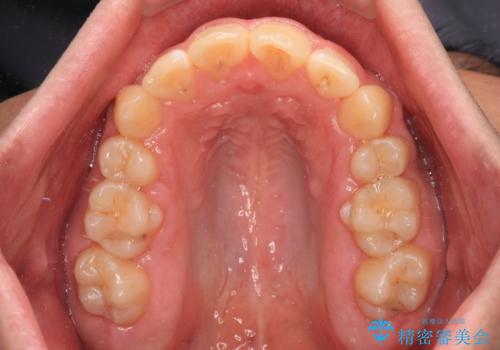

上顎歯列全体がスムーズに後方移動でき、1年で治療を終えることができました。